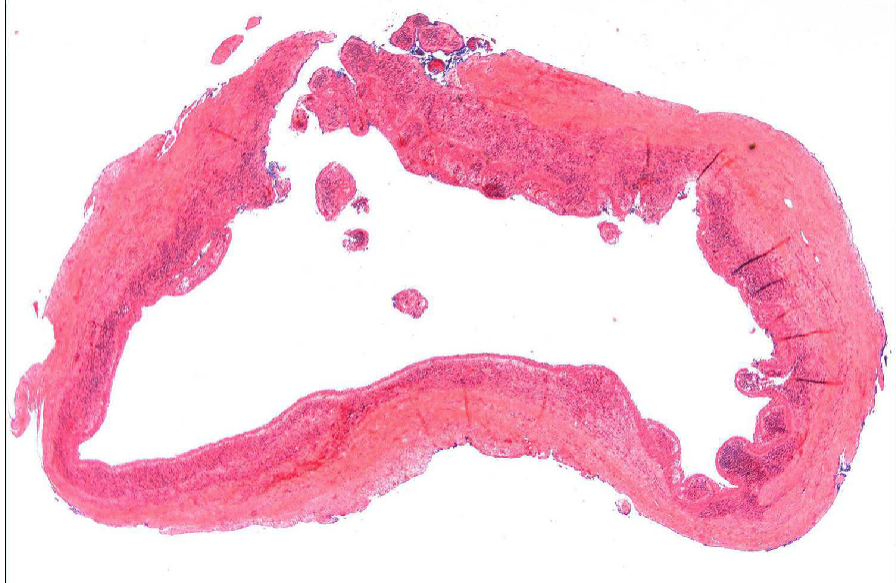

describe the 3 structural components of a cyst

outer → inner

fibrous CT + granulation tissue

epithelium

lumen

T/F: periapical cysts are the most common odontogenic cyst

true

how does the epithelium form the lining of a periapical cyst

usually derived from rests of Malassez or from lateral aspect of root at orifice of accessory canal

2 histopath features of periapical cysts

lining of cyst composed of stratified squamous epithelium

wall of cyst consists of dense fibrous tissue w/ inflammatory infiltrate